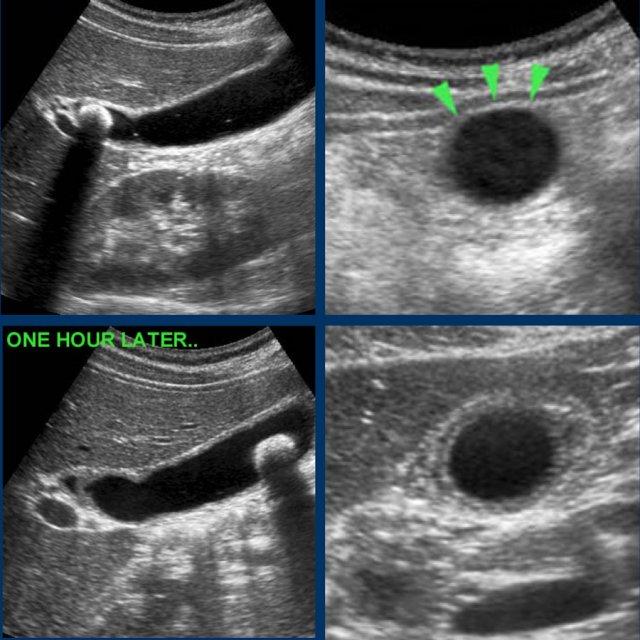

Hình ảnh của một phụ nữ trẻ bị cơn đau quặn mật kéo dài 8 giờ.

Siêu âm cho thấy sỏi bị kẹt và phù nề túi mật.

Bệnh nhân đi bộ trong một giờ và siêu âm được thực hiện lại.

Sỏi đã bong ra, và phù nề tái tưới máu xuất hiện như những dấu hiệu chứng nhân thầm lặng của cơn đau quặn.

CRP vẫn bình thường.

Khi phù nề túi mật đã biến mất, bệnh nhân không còn đau quặn nữa.